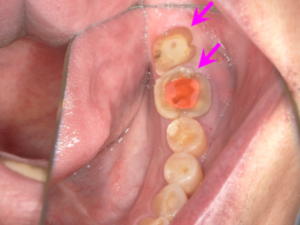

仮歯を装着後に、左下の奥歯の歯ぐきに炎症が出現しました(矢印部)。

左下の奥歯のレントゲン写真です。

炎症は改善したものの、歯ぎしりが強く歯の根が破折してしまいました。

歯ぎしりが強く、歯を削るブリッジでの治療は同様に治療した歯の破折を招く可能性が高いため、この部分もインプラント治療を行うこととしました。